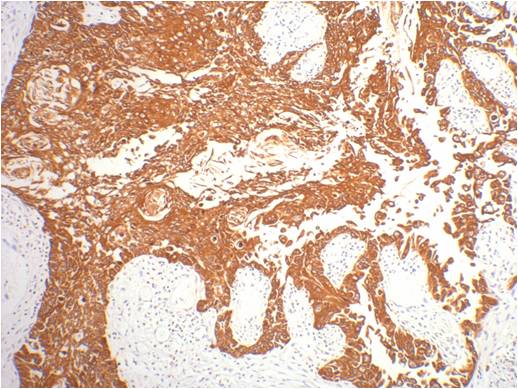

Product name: CK16 Mouse mAb

Alternative Names: Cytokeratin 16, K16, K1CP, keratin 16, KRT16, KRT16A, NEPPK

Dilutions: IHC 1:200

Background: Keratin 16 is expressed in keratinocytes, which are undergoing rapid turnover in the suprabasal region (also known as hyperproliferation-related keratins). Keratin 16 is absent in normal breast tissue and in noninvasive breast carcinomas. Only 10% of the invasive breast carcinomas show diffuse or focal positivity. Reportedly, a relatively high concordance was found between the carcinomas immunostaining with the basal cell and the hyperproliferation-related keratins, but not between these markers and the proliferation marker Ki-67. This supports the conclusion that basal cells in breast cancer may show extensive proliferation, and that absence of Ki-67 staining does not mean that (tumor) cells are not proliferating.